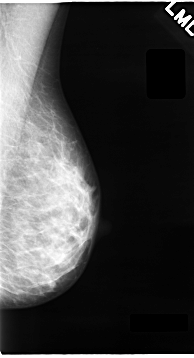

C_0063_1.LEFT_CC

LEFT_CC LINES 4632 PIXELS_PER_LINE 2416 BITS_PER_PIXEL 12 RESOLUTION 50 NON_OVERLAY